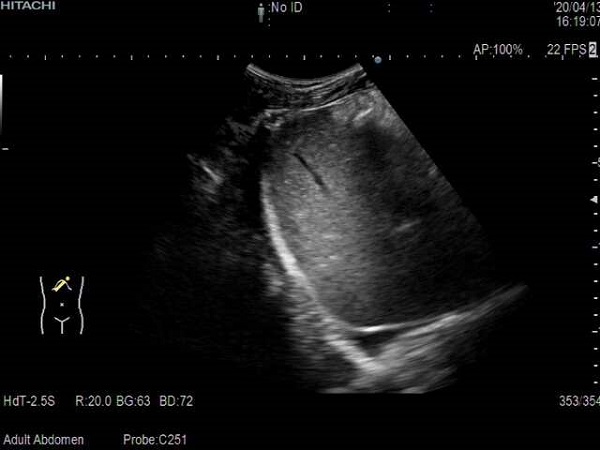

连通注射器,瞬间抽出大量黄色浓稠脓液,随着积存于腹腔的大量脓液的引出,患者症状得到极大的改善。

顺利抽出脓液